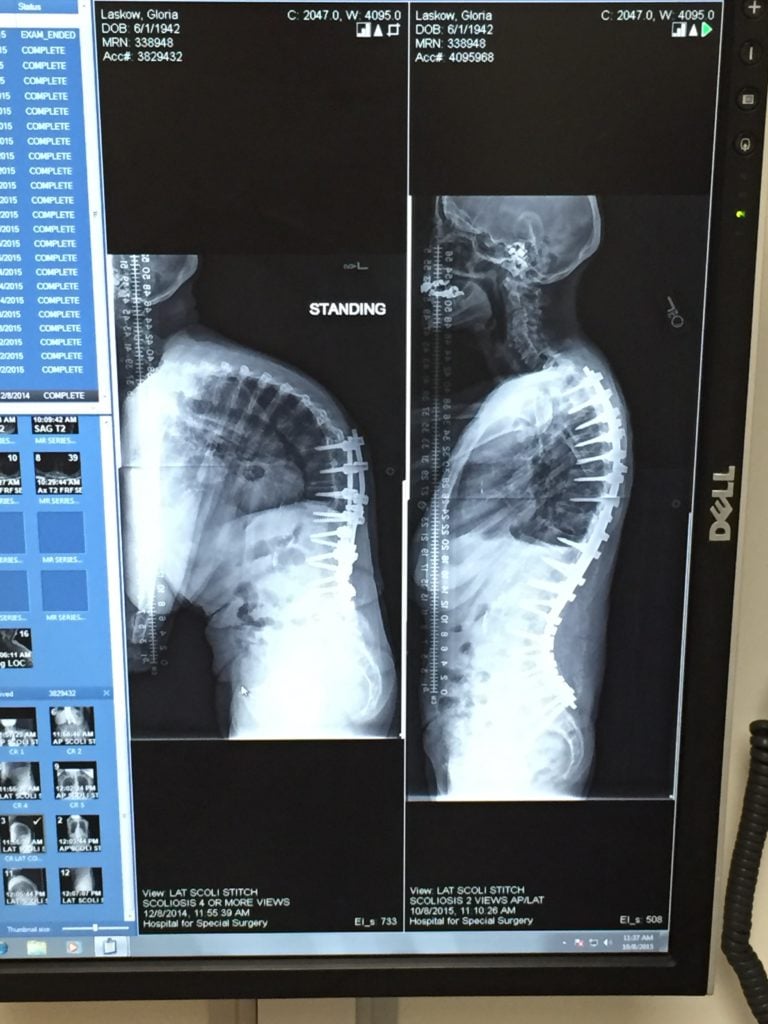

Dr. Lebl performed my surgery approximately 2 years ago. I had a lumbar fusion L4/5. Prior to this surgery, I had had 2 lumbar surgeries. One was a lumbar microdiscectomy L5/S1 and the other was a laminotomy L5/S1. Those two surgeries were performed by another prominent surgeon in NYC. The first surgery was done in 2008 and was successful. In 2014, I had a disc collapse and received the second surgery with the same surgeon I used the first time, thinking it would be successful as well. However, the second surgery didn't take away my pain and the pain got worse. I must mention that I am a very active 54 year old woman. I used to run every day and go to the gym on a daily basis. I enjoyed spin classes as a well as hot yoga. I was truly obsessed with exercise. To not be able to do most of the things I enjoyed was truly devastating. Prior to Dr. Lebl performing the 3rd surgery, I literally could not walk more than a block. I also had scoliosis with an 83 degree curve in my spine! I did much research on surgeons and I read about Dr. Lebl and set up a consult. I had seen many surgeons in NYC prior to Dr. Lebl. From our first meeting Dr. Lebl was extremely professional and quite confident in his solution in fixing my problem. He did not waiver and explained in terms we could understand what he was going to do. Dr. Lebl was not arrogant as many of these surgeons can be. Also, many other doctors would have shied away from doing my surgery, because I had two previous surgeries and very severe scoliosis. Not Dr. Lebl, he was more than up for the challenge and gave me a very good success rate. Dr. Lebl was also concerned because I had very low bone density and told me to see the metabolic bone doctors at HSS. This is where I met Patricia Donahue, N.P. Ms. Donahue identified my issues and was very concerned that I may not fuse due to the bone density being so low. She worked out a plan for me, very quickly I might add, so that the surgery would be a success. Her kindness and brilliancy was unparalleled. She even came to the hospital to visit me after my surgery. My surgery was performed in April 2017. I am not going to lie, recovery was very tough and there were times when I felt like throwing in the towel. Dr. Lebl kept telling me to be patient, things would improve. I would also add that when you called Dr. Lebl's office with concerns after the surgery, you were never ignored as some doctors would do. With a lot of handwork, on strengthen the back muscles and core, as Dr. Lebl said this was key, I can finally say that I am so so glad I go the surgery. Dr, Lebl gave me my life back truly he did! I am now enjoying all the things I used to love! Prior to the surgery, I could not even sit on my own couch. Now I can sit anywhere! I can go on vacation and go see my children at college without pain! I cannot thank Dr. Lebl and Patricia Donahue, N.P. enough !